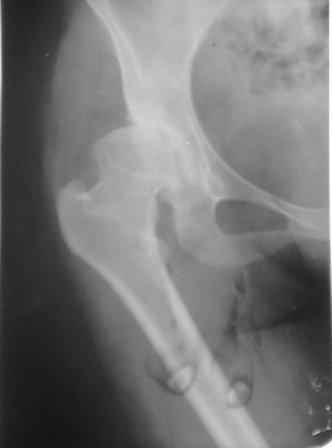

При определении показаний к м/в остеотомии учитываем не только функциональное состояние, но анатомическую форму сустава. Например, при той форме, что на картинке в вашем письме (мелкая впадина,уже не сферичная головка)НИИТО вполне обосновано предлагает ТЭП. Варизирующая остеотомия в "чистом виде" усилит конфликт в опорной зоне сустава. Если очень "настоятельно просит" - экстензия с наружной ротацией по R.Bombelli. То есть на открытом суставе бедро согнуть и ротировать внутрь до покрытия головки впадиной. Сформировать канал через шейку в головку с тем расчетом, что после м/в распила бедро нужно вывести в функциональное положение. Фиксировать 90 град. медиализирующей ортопедической пластиной с клинком. Но выздоровления не обещать, покрытие головки малое, длительного эффекта не будет. Нужна периацетабулярная остеотомия или пластика крыши, но это другая сложность и другая травматичность. Необходимость ТЭП оттянете лет на 10 в лучшем случае. Надо учитывать, что в этом случае ТЭП операция не первая, это увеличивает инфекц. риски и снижает функциональный результат для сустава. Я бы рекомендовал трость с противоположной стороны, ЛФК на приведение, чтобы подрос оссификат крыши и сформировались оссификаты головки. При нормотрофическом типе поражения можно будет провести вальгизирующую остеотомию, эффект которой более длительный или больная за это время найдет возможности приобретения ЭП.

Типичная концовка проигнорированного диспластического состояния сустава. Дисплазия тазобедренного сустава часто встречающаяся патология у жителей Центральной Азии вследствие тугого пеленания в детстве. Традиционно ребенок находится в течение дня в так называемой кроватке "бешик", удобной в быту, но она впоследствии приводит к недоразвитию тазобедренного сустава.

Это первые признаки начала деструкции сустава, и возможно, аналгетики помогут для купирования болей, но в течение очень короткого времени от сустава ничего не останется, и в дальнейшем останется только артропластика.

При более сохранном суставе от дальнейшего разрушения можно было бы сохранить только периориентацией нагрузки на сустав - Периацетабулярной Остеотомией .

Данный сустав в начальной стадии разрушения, но все-таки я бы сделал обзорный таз и отдельные снимки сустава в 30 градусной абдукции и аддукции. Также снимки с внутренней и наружной ротацией для оценки состояния головки бедра.

Представляю Р-снимки: обзорная, с отведением и с приведением.

Глубокоуважаемый Игорь Владимирович! Признаюсь допустил ошибку, из-за напряженности работы и нехватки времени, когда повторно внимательно посмотрел все понял и не успел исправить ошибку до Вашего поста, конечно скошенность крыши в пределах 40гр,часть головки кнаружи линии Омбредана-Перкинса , облитерация дна вертлужной впадины и т.д.-это ДМВБ.